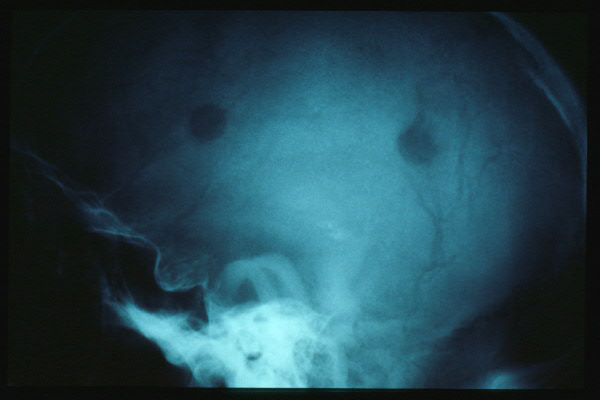

Estómago en cascada al TEGD.